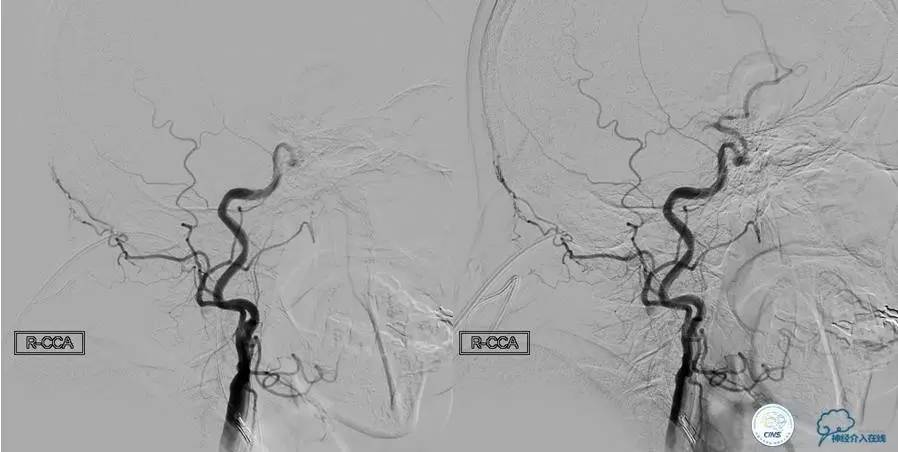

▼L-CCA

▼R-VA